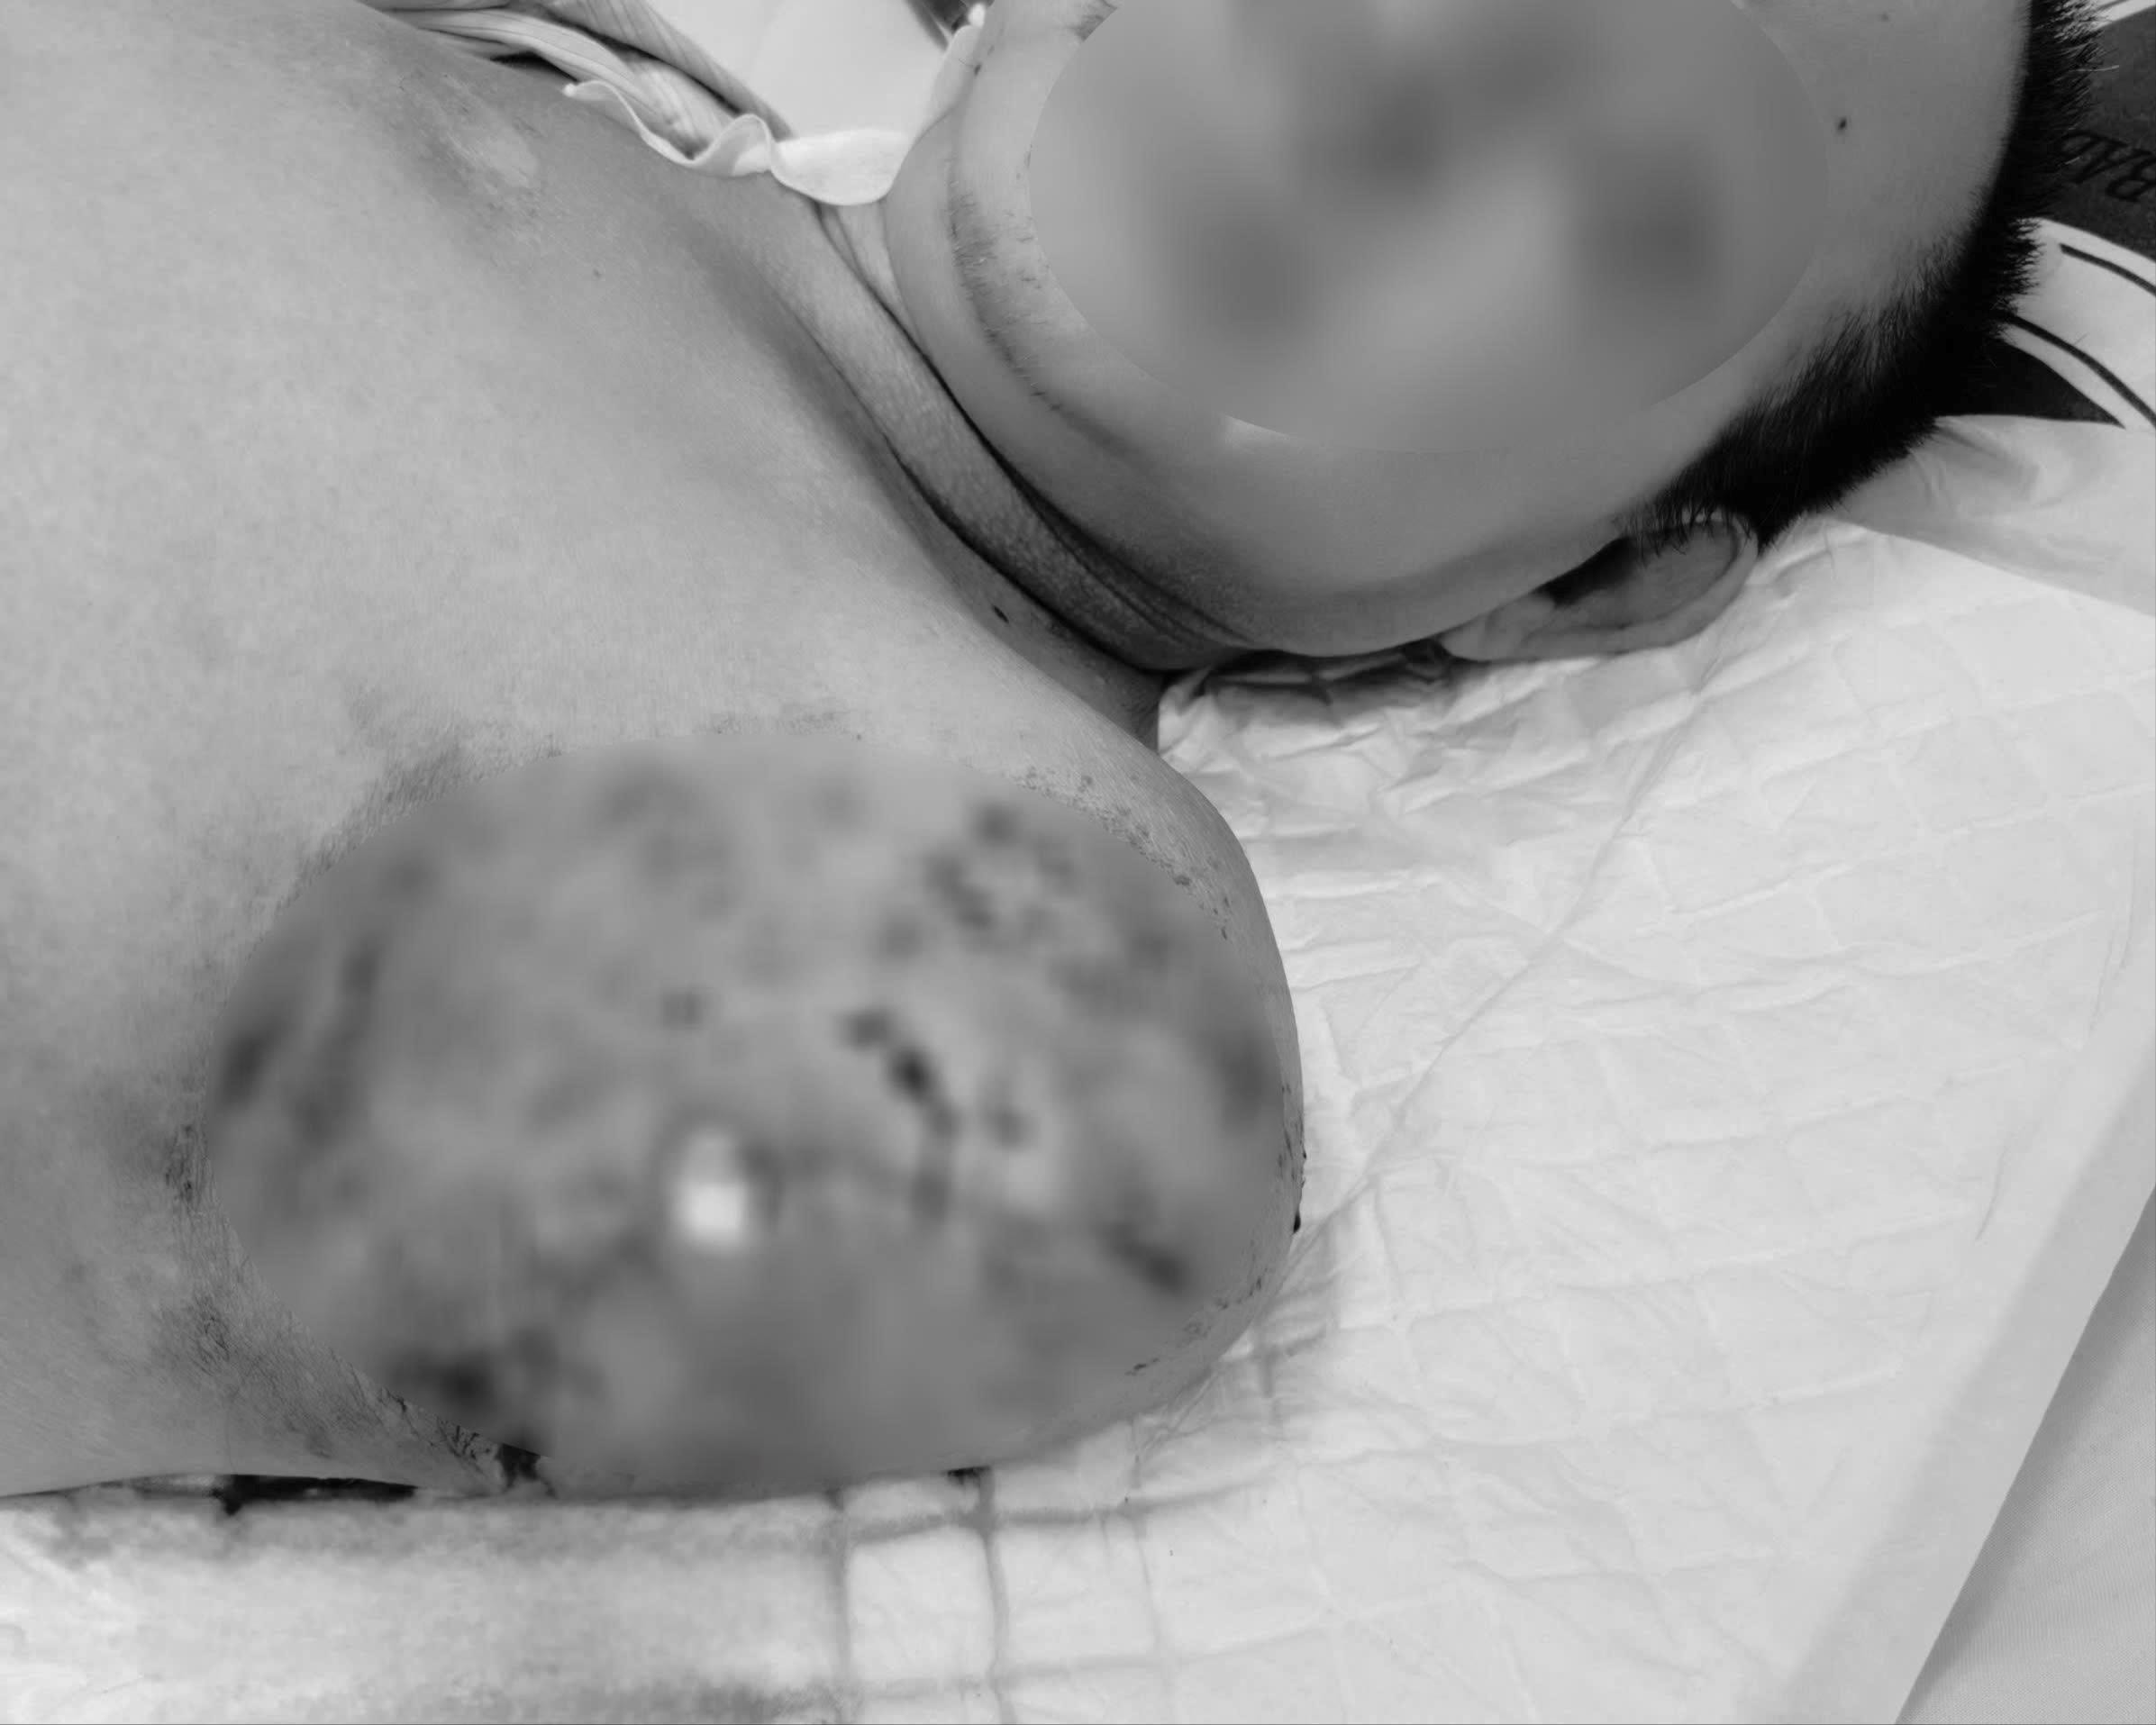

200 y lệnh, 93 cuộc hội chẩn cứu sống bệnh nhân hoại tử toàn bộ cánh tay trái

(CLO) 47 ngày điều trị là chuỗi ngày căng thẳng nghẹt thở với hơn 200 y lệnh, gần 300 kết quả xét nghiệm, 93 cuộc hội chẩn trong và liên chuyên khoa, cùng 2 ca phẫu thuật sinh tử cứu sống bệnh nhân bị sốc nhiễm khuẩn nặng, tụt huyết áp sâu.